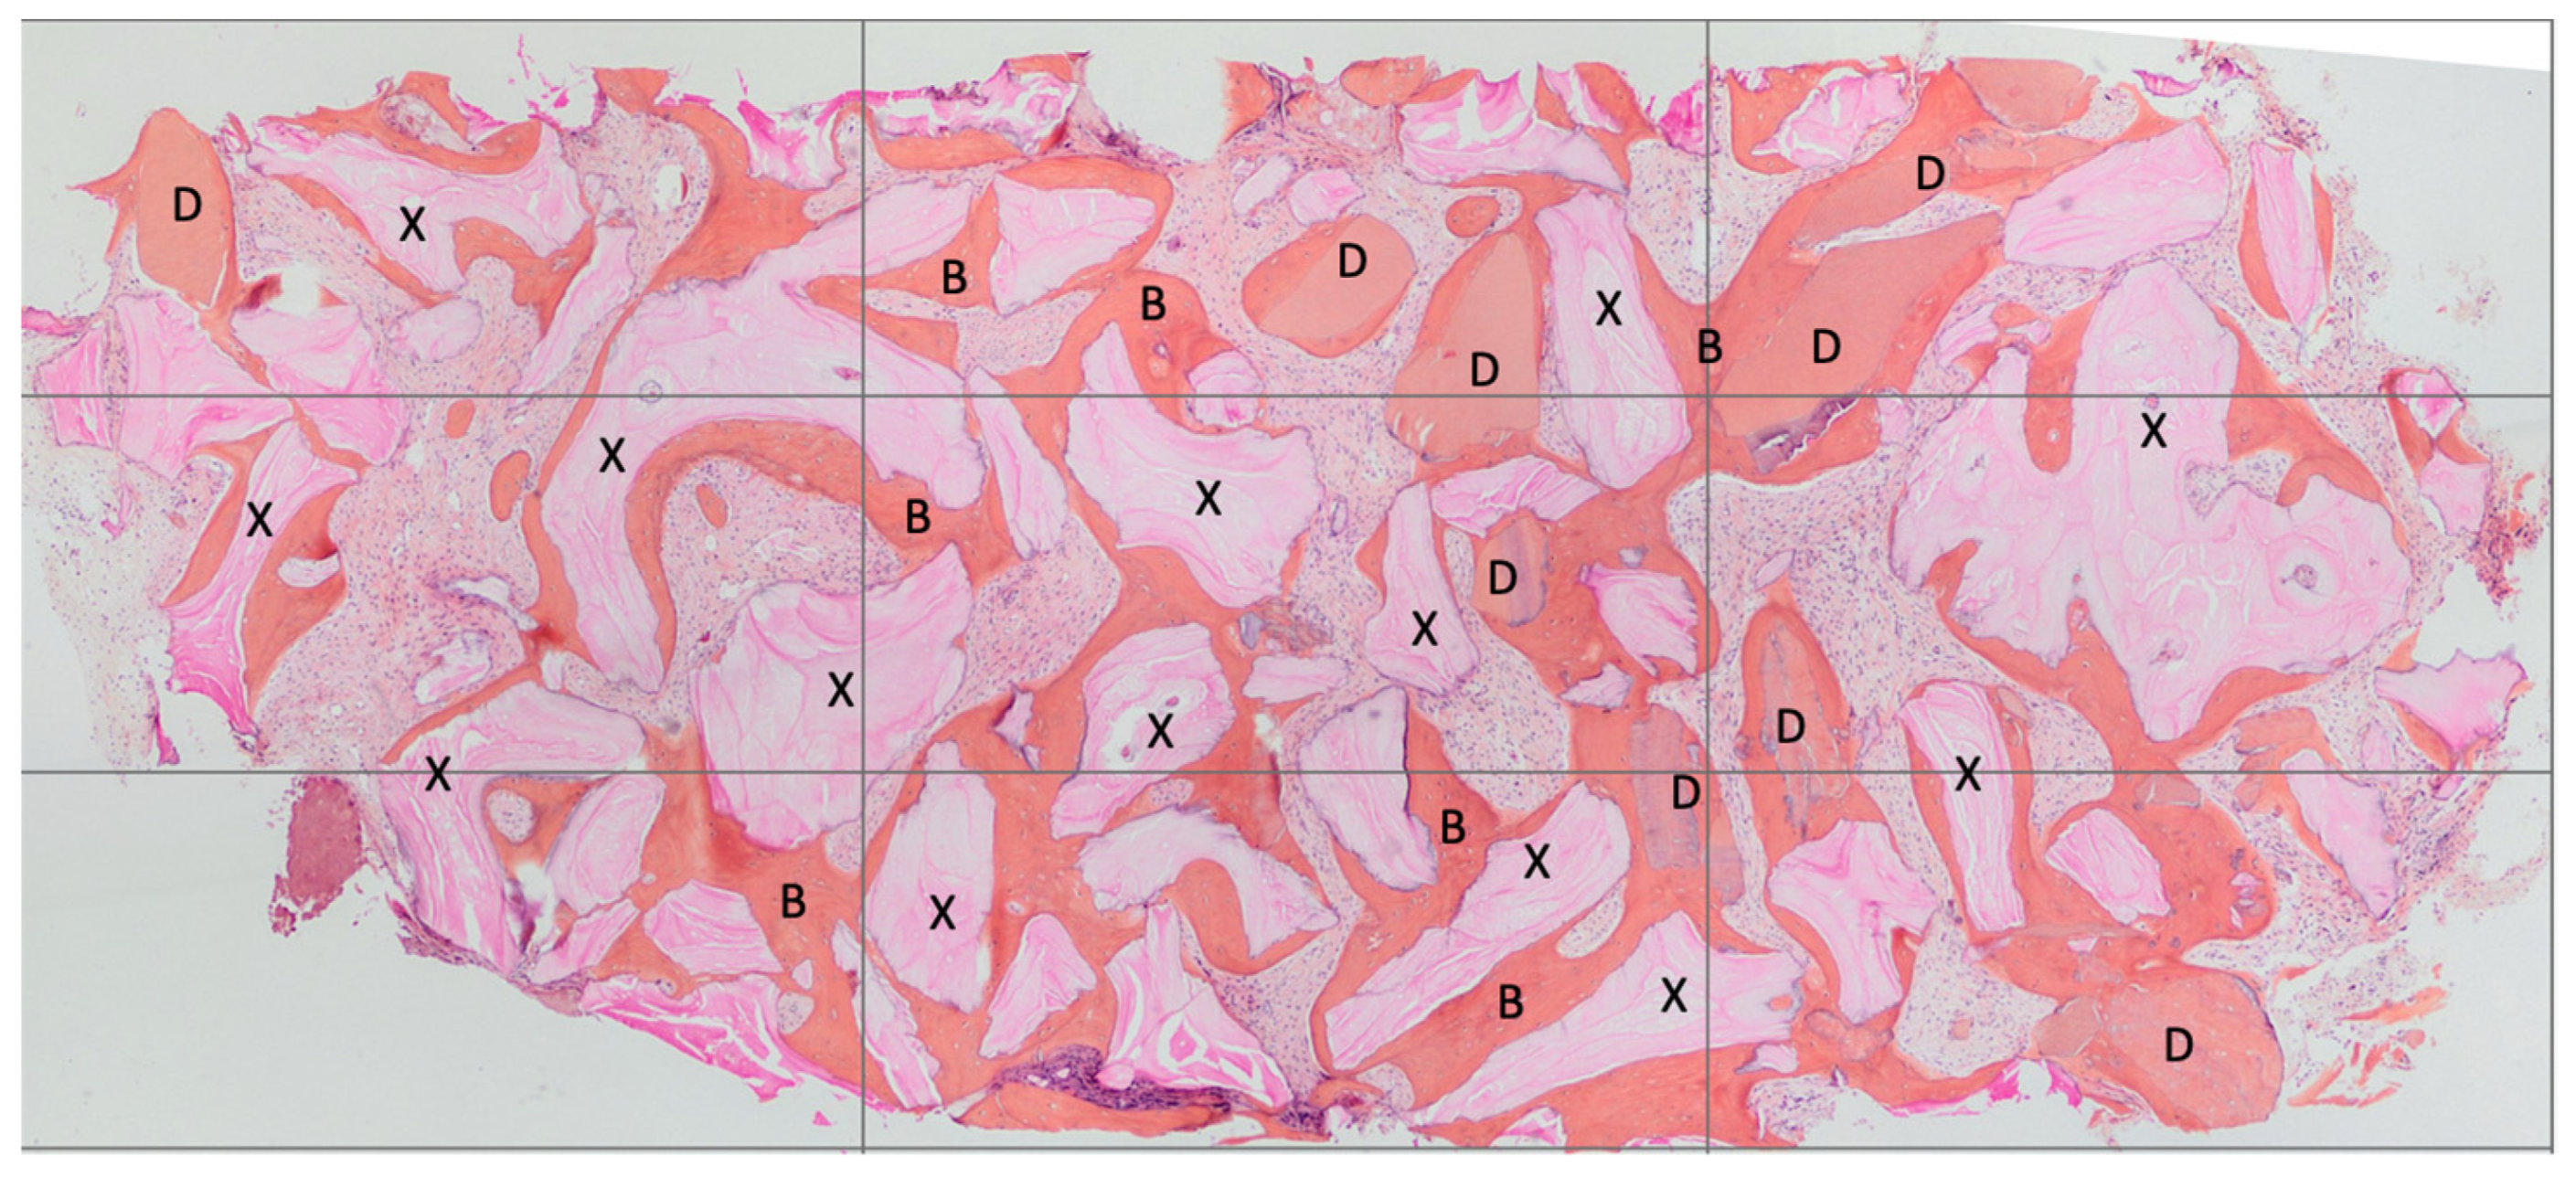

2.6. Histological Technique

- Decalcified:

- BV%: Percentage of mineralized tissue excluding medullary tissues.

- Graft%: Percentage of the volume occupied by the remaining graft or dentin.

- VB%: Percentage of vital bone excluding medullary tissues. The sum of TT% and VB% represented the BV%. Each subsection was measured using the ImageJ 1.52q program.

- Non-decalcified:

- BV% = Percentage of residual bone volume, excluding medullary tissues;

- Graft% = Percentage of the remaining graft, without bone and marrow;

- VB% = Percentage of vital bone, excluding the bone marrow and the residual graft.

| BV% | NB% | Residual Graft Dentin % | Dentin Loss Percentage | Residual Graft Bio-Oss % | Bio-Oss Loss Percentage | |

|---|---|---|---|---|---|---|

| 4 Months | 65.66% | 29.03± 6.57% | 8.68 ± 3.36% | 71% | 27.95 ± 5.23% | 6.74% |

| 8 Months | 59% | 34.12 ± 5.05 | 2.79 ± 1.48 | 90.71% | 22.09 ± 13.81 | 26.42% |